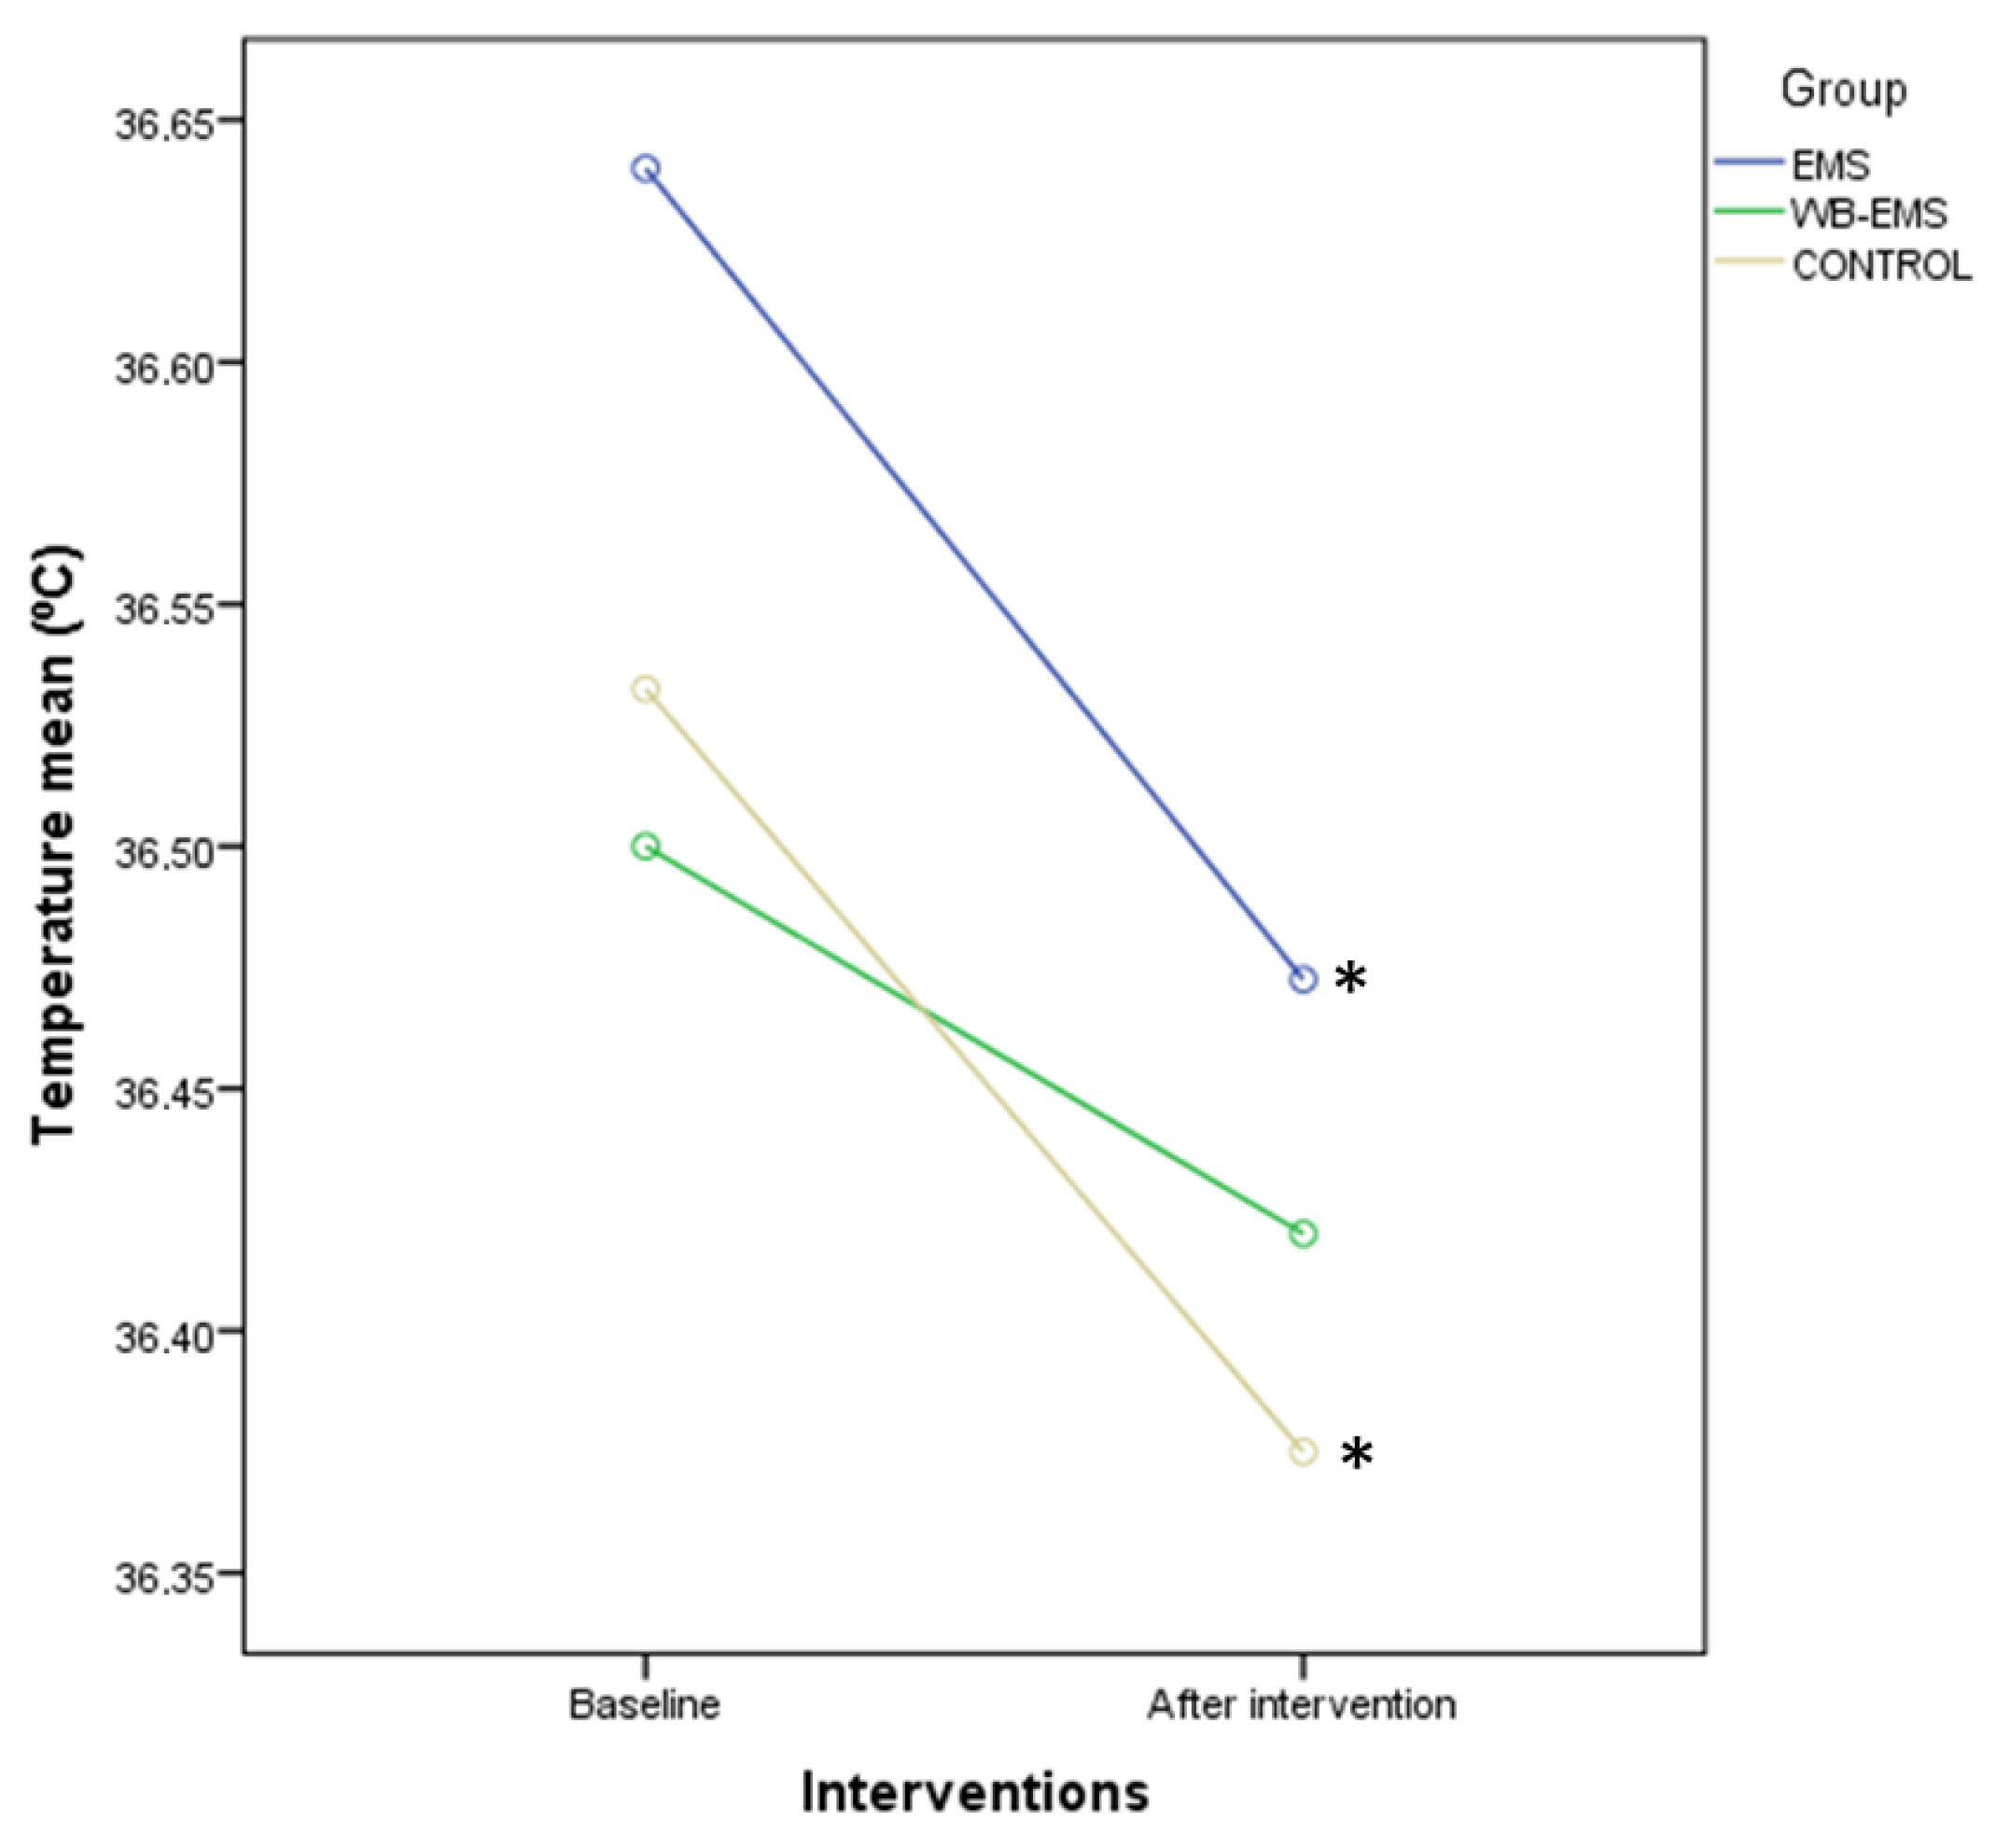

3.3. Outcome Measurements Differences after Interventions

3.4. Two-Way ANOVA of Repeated Measurements for Intra- and Intergroup Comparisons

| Temperature (°C) | 36.65 ± 0.30 (36.40–36.90) | 36.60 ± 0.40 (35.70–36.90) | 36.60 ± 0.18 (34.60–36.80) | 0.050 † |

| Temperature (°C) | 36.65 ± 0.30 (36.40–36.90) | 36.55 ± 0.30 (36.80–37.20) | −0.10 ± 0.40 (−1.60–0.70) | 36.60 ± 0.40 (35.70–36.90) | 36.50 ± 0.38 (35.00–37.90) | −0.10 ± 0.48 (−1.30–1.10) | 36.60 ± 0.18 (34.60–36.80) | 36.50 ± 0.48 (34.60–36.90) | −0.10 ± 0.50 (−2.00–2.00) | 0.755 † |